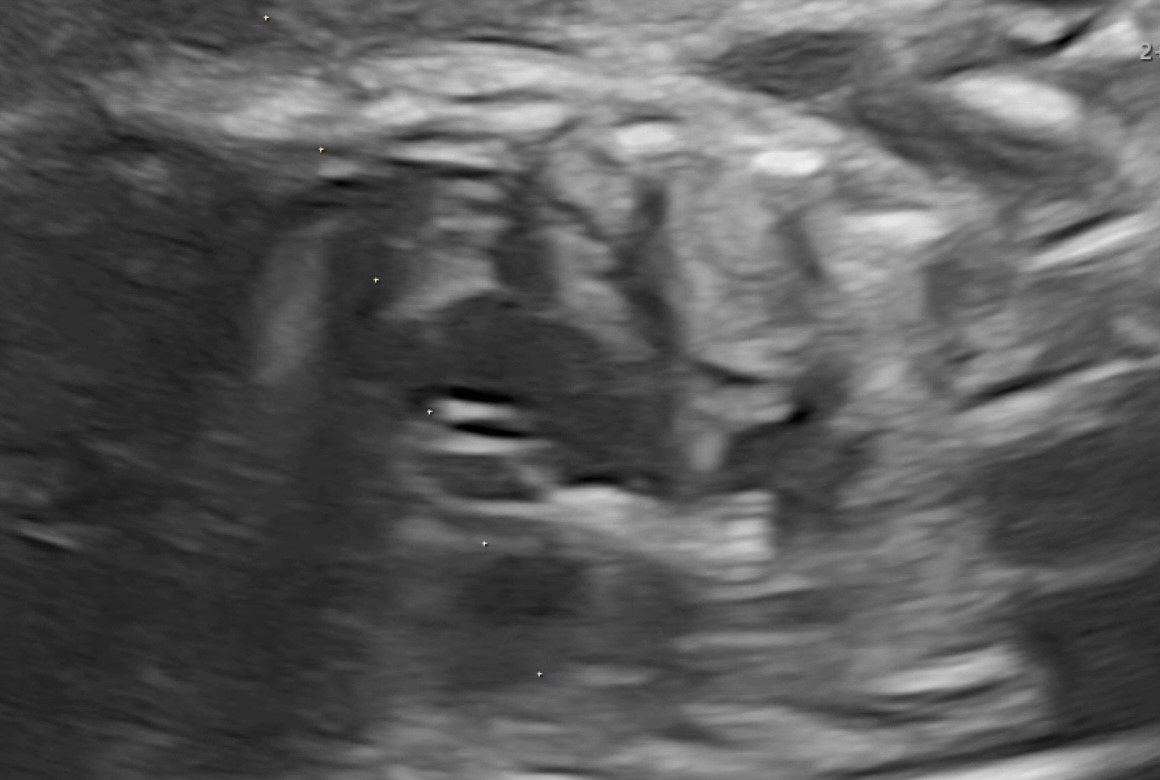

3 a. до выполненной вальвулопластики клапана аорты

3 b. после выполненной вальвулопластики клапана аорты и извлечения баллона с иглой

По данным ультразвукового исследования после выполненной вальвулопластики клапана аорты и извлечения баллона с иглой отмечается увеличение эффективного отверстия клапана аорты и отсутствие жидкости в полости перикарда.

Через 12 часов после операции было проведено ультразвуковое исследование сердца плода. Фракция выброса ЛЖ увеличилась до 24 %, диаметр эффективного отверстия АК составил 2,9 мм. Максимальный градиент на АК возрос до 21 mm Hg, митральная регургитация уменьшилась с тотальной до 2 степени. Жидкости в полости перикарда обнаружено не было.